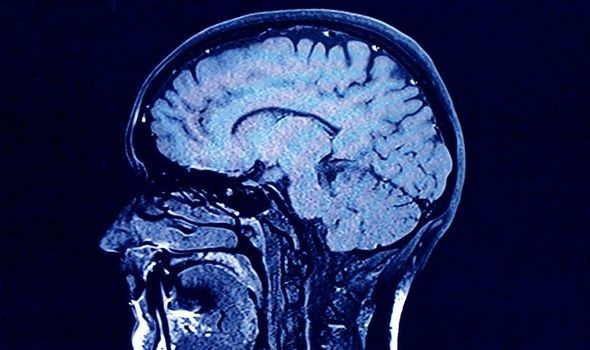

Theo nghiên cứu mới, các nhà thám hiểm không gian đang phải đối mặt với nhiều nguy hiểm tiềm tàng khi du hành một quãng đường dài. Nhiều nhà khoa học cho rằng, bộ não của họ có thể bị phình to trong môi trường chân không.

Trong những thập kỷ tới, nếu người Trung Quốc hay NASA tìm cách đưa con người lên sao Hỏa, các cơ quan vũ trụ này có lẽ sẽ phải đánh giá lại chiến lược của mình sau khi những nghiên cứu mới nhất phát hiện ra việc du hành vũ trụ gây tổn thương cho cơ thể con người, đặc biệt là não. Nghiên cứu mới cho thấy bộ não của con người có thể bị phình ra trong điều kiện vi trọng lực. Điều này là do, khi ở Trái đất, trọng lực giúp máu chảy điều hòa trong cơ thể. Ngược lại, trong không gian, máu bắt đầu chảy trong các dây thần kinh thị giác cùng với lượng chất lỏng dư thừa làm tăng thể tích thực tế của não.

Các nhà khoa học từ Đại học Texas đã thực hiện 10 lần quét não MRI trên các phi hành gia trước và sau khi họ dành thời gian trên Trạm vũ trụ quốc tế. Nhóm nghiên cứu phát hiện ra rằng việc tiếp xúc lâu với vi trọng lực đã gây ra sự giãn nở trong não và dịch não tủy - chất lỏng trong suốt hoạt động như một bộ đệm cho não. Theo các nhà nghiên cứu, những thay đổi trong não này có thể so sánh với một người đã trải qua một thời gian dài trên giường bệnh.

Những hệ lụy lâu dài của việc này đối với các phi hành gia vẫn chưa đưa được ra kết luận đầy đủ, nhưng các nhà nghiên cứu cho biết: "Hiện tượng tương tự với một loại bệnh được gọi là tràn dịch não, tình trạng này xảy ra khi tâm thất trong não bị phình to bất thường. Các triệu chứng của tình trạng này bao gồm khó đi lại, gặp khó khăn trong việc kiểm soát bàng quang và mất trí nhớ.” Cho đến nay, các triệu chứng này vẫn không được đưa vào báo cáo của các phi hành gia sau khi du hành vũ trụ.

Larry Kramer, giáo sư tại Trung tâm khoa học sức khỏe của Đại học Texas ở Houston và là tác giả chính của nghiên cứu, cho biết: Khi bạn ở trạng thái vi trọng lực, chất lỏng như máu trong tĩnh mạch của bạn không còn chảy về phía chi dưới mà phân phối đi khắp nơi. Sự chuyển động của chất lỏng về phía đầu có thể là một trong những nguyên nhân gây ra những thay đổi mà chúng ta đang quan sát thấy trong mắt và khoang nội sọ của các phi hành gia. Trên thực tế, sự mở rộng vật chất sẽ chịu trách nhiệm cho sự gia tăng khối lượng não và dịch não tủy. Loại biến dạng này phù hợp với việc tiếp xúc với áp lực lớn”.